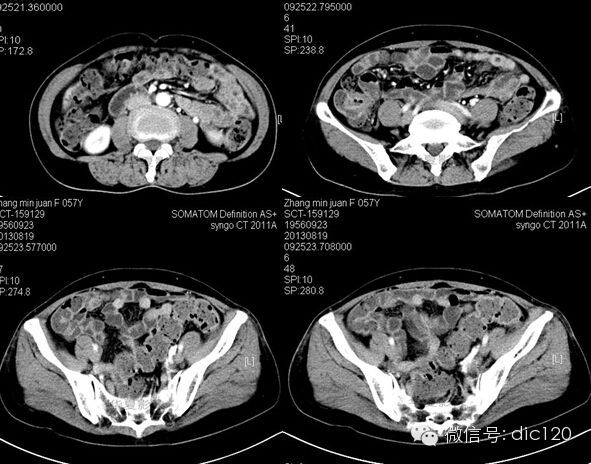

F,56Y,左腰腹部疼痛3天,B超:左肾积水,左输尿管上段扩张。

结果:卵巢静脉综合征,患者有外压性输尿管梗阻,卵巢静脉与输尿管交叉处有粘连。